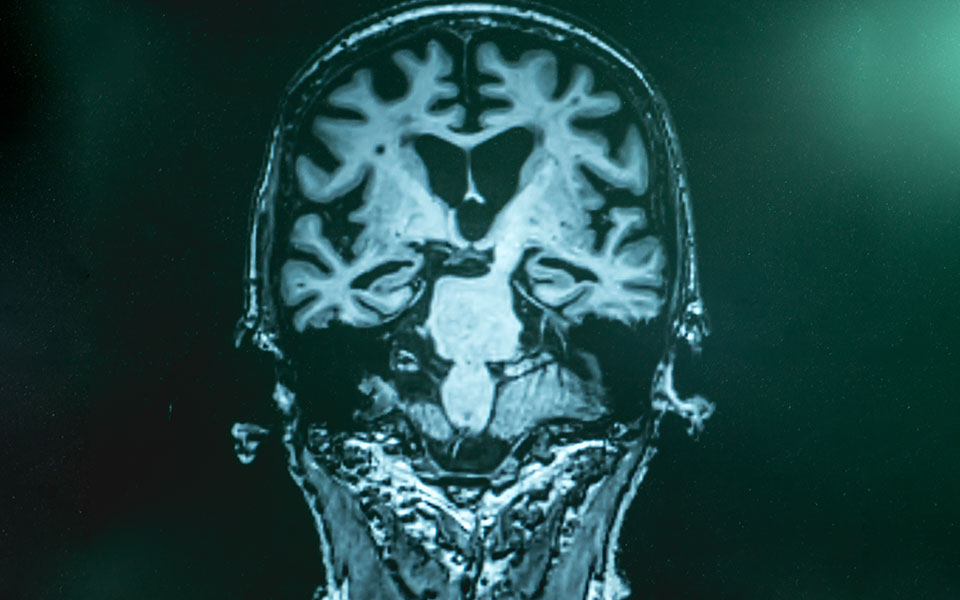

– Η νόσος Αλτσχάιμερ είναι μια μορφή γεροντικής άνοιας, με πολύ περισσότερους ασθενείς από τις άλλες μορφές άνοιας.

– To aducanumab είναι ένα αντίσωμα που αναγνωρίζει και συνδέεται με τις πλάκες του αμυλοειδούς, την «υπογραφή» του Αλτσχάιμερ στον εγκέφαλο. Σύμφωνα με μία θεωρία, η ασθένεια εμφανίζεται λόγω της συγκέντρωσης στον εγκέφαλο πλακών βήτα αμυλοειδούς που εκφυλίζουν τα κύτταρα. To aducanumab τις αναγνωρίζει και βοηθάει στη διάσπαση και στην εκκαθάρισή τους. Το φάρμακο, θεωρητικά, καθυστερεί τον εκφυλισμό του εγκεφάλου. Θεωρητικά πάλι, αν χορηγηθεί στον ασθενή έγκαιρα θα αποτρέψει την εμφάνιση των πιο σοβαρών συμπτωμάτων. Εχουμε, ωστόσο, πολύ δρόμο μπροστά μας προτού κατανοήσουμε καλύτερα τον τρόπο δράσης και την αποτελεσματικότητα του φαρμάκου. Πάντως, το aducanumab είναι το πρώτο φάρμακο για το Αλτσχάιμερ που σε κλινικές δοκιμές κατέγραψε θετικά αποτελέσματα, τα οποία ενισχύονται με τη δόση ή τον χρόνο χρήσης και συνδυάζει μερική εξάλειψη των πλακών και επιβράδυνση της έκπτωσης της πνευματικής διαύγειας των ασθενών.